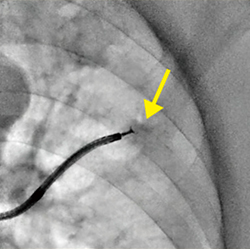

症例1 新画像処理条件の透視像。病変(↓)および生検鉗子ともに明瞭に見える。